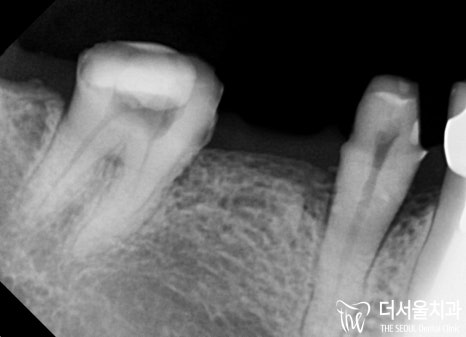

『네비게이션 임플란트 및 신경치료』

자연치를 더 이상 살릴 수 없었던 곳은

네비게이션 임플란트 를 통해

안전하고 신속하게 과정을 마무리했습니다.

이와 더불어 신경치료도 함께 진행했는데요.

뿌리 끝까지 확실하게 채워져야

더 오래오래 건강하게 사용하실 수 있기에!

고도의 집중력을 발휘하여 밀폐를 시켰죠ㅎㅎ